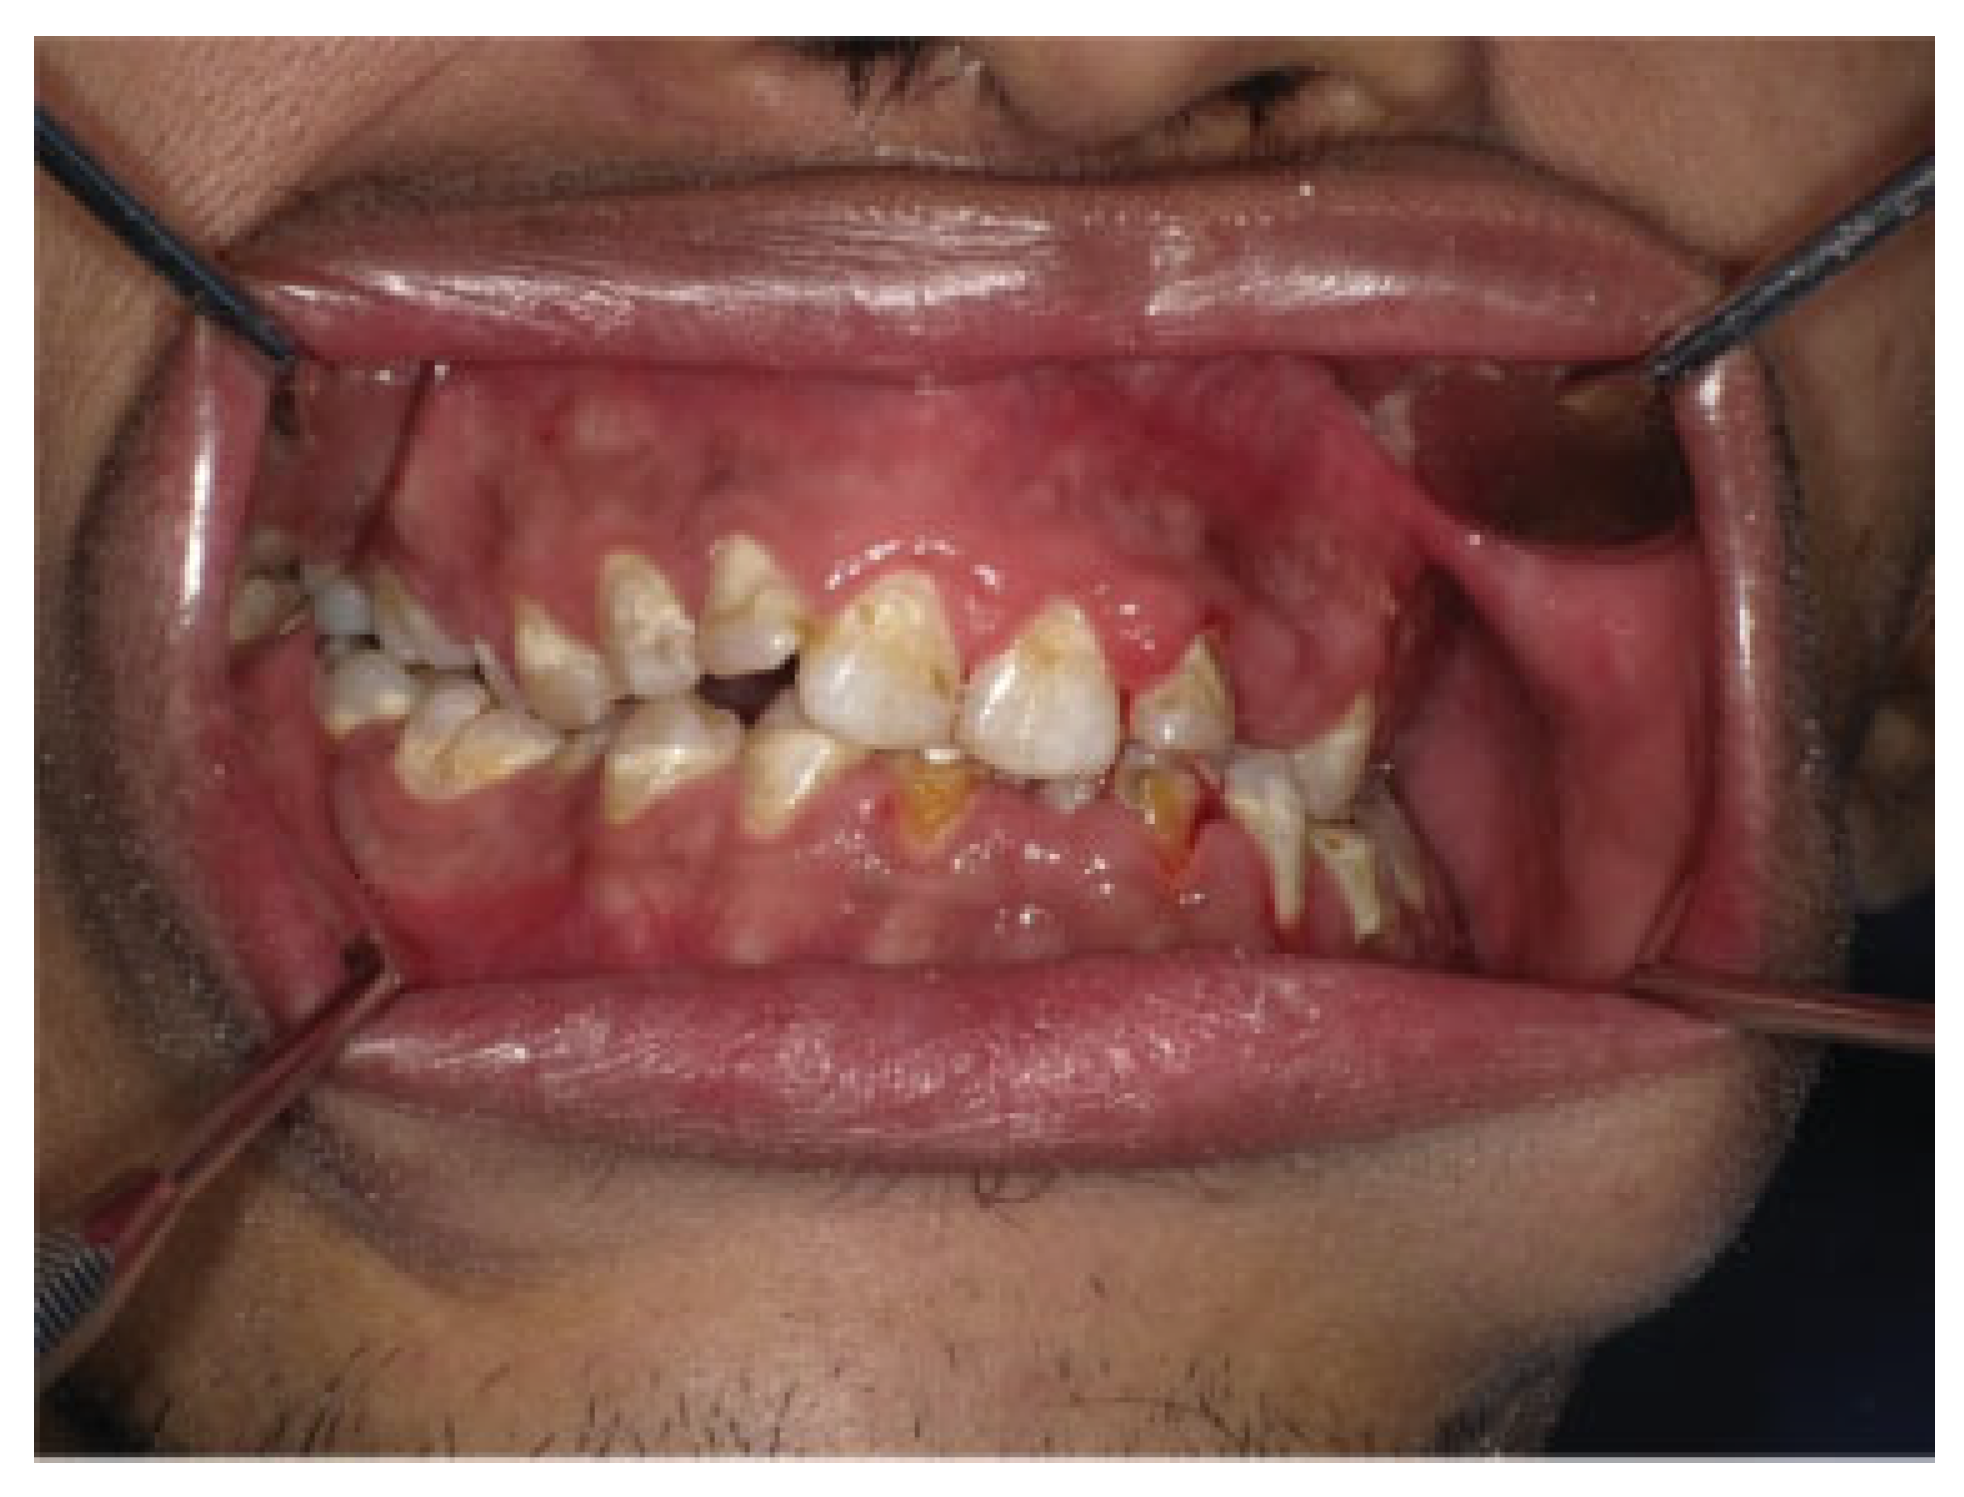

Arch bars were applied to upper and lower teeth. The patient was subjected to 2 weeks of intermaxillary fixation (IMF) to keep the condyles in new position and then continued on elastics training. CT scan immediately postoperative shows the right condyle inferior to the articular eminence and the left condyle inferior to the left glenoid fossa ([Figure 5]). Postoperative 1 year review shows satisfactory occlusion ([Figure 6]). Masticatory function of patient has returned to normal and he was able to take normal diet. No recurrence of the TMJ dislocation was recorded.

Figure 6. Postoperative 1 year review showed satisfactory occlusion.